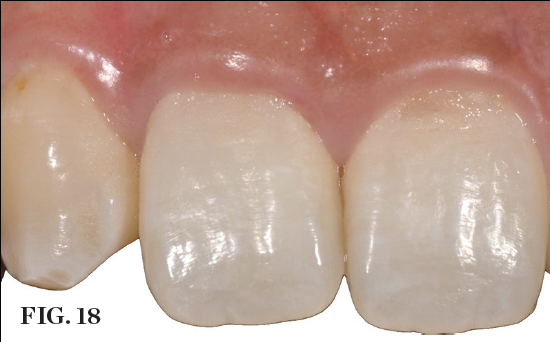

(18.) Postoperative view 3 months after provisional restoration. Note the ideal tissue anatomy that was created through correct implant positioning and immediate transmucosal guidance.

Figure 18